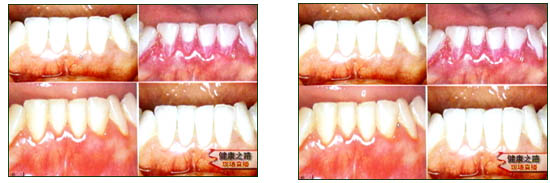

主持人:整个牙周病的发病过程是怎样的? 章锦才:口腔与外界环境是相通的,里面有大量的细菌,如图沉积在牙颈部的细菌会产生大量的毒素,毒素会刺激牙龈组织发炎,牙龈组织发炎后就会出现充血、水肿、炎性细胞渗出,临床就会表现牙龈的肿、红、疼痛、出血等症状,如果炎症仅仅局限于牙龈,这时治疗是可逆的,恢复起来也比较好,牙龈完全可以恢复到一个正常的结构。如果这时炎症没有控制好,继续向深部发展,就会引起牙槽骨的破坏和牙周膜的破坏,这就是典型的牙周炎的症状,牙周炎早期牙齿不一定有松动,到了晚期就会出现松动。 沙月琴:来看一组图:左上角是一个很健康的牙周组织,一旦停止口腔卫生,十天以后(右上图)牙颈部就堆积了大量的菌斑,左下角图中可以看到牙龈已经发肿,边缘也变厚了,颜色已经发红,这说明已经有了牙龈炎了,恢复口腔卫生措施(刷牙)后,右下图中可以看到牙龈颜色和各方面完全已经恢复正常了,这也充分说明了细菌确实是引起牙周病的罪魁祸首。